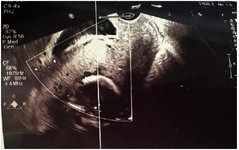

At 29 weeks of gestation, the patient experienced a mild vaginal bleeding episode and was admitted to Imam Reza Hospital. Ultrasound confirmed persistent placenta percreta (Figure 2). Vital signs were stable. She received neuroprotective magnesium sulfate and two doses of betamethasone for fetal lung maturity. After 72 hr, the bleeding resolved, and she was discharged with instructions for close monitoring and immediate return if symptoms recurred.

Figure 2. Ultrasound image demonstrating loss of interface between the myometrium and placenta, with increased vascularity behind the placenta and presence of multiple placental lakes, consistent with placenta percreta